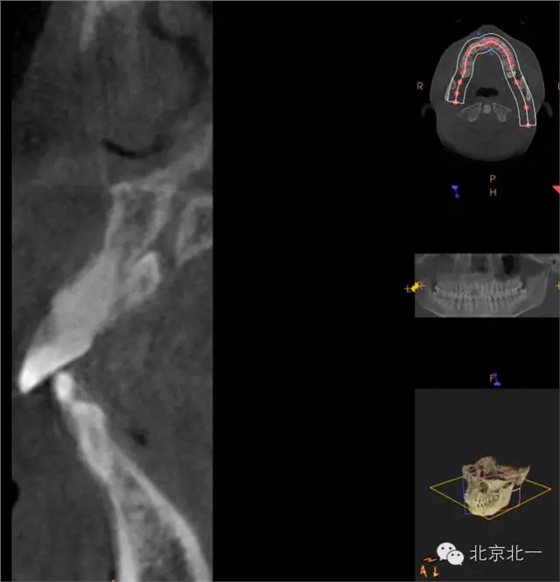

CBCT冠狀位顯示多生牙位于鼻腭神經(jīng)管

三維重建效果圖